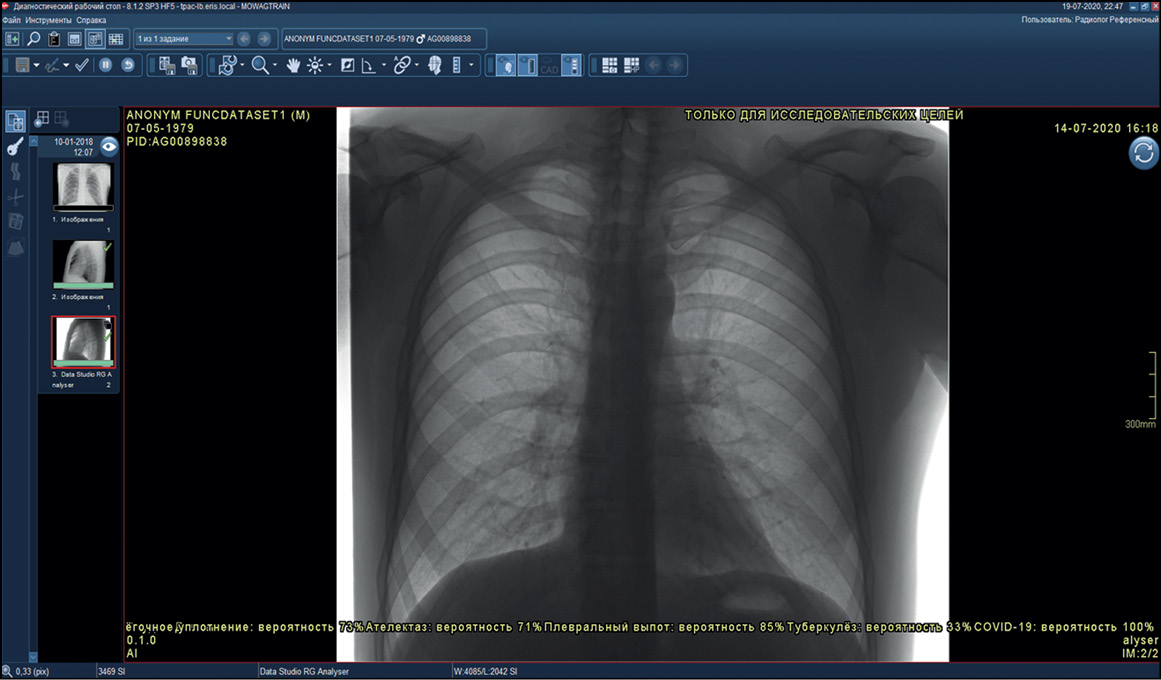

Functional testing is a stage wherein software functions specified by a supplier are checked for availability and functionality. This testing is performed at the technical and clinical levels. On a technical level, the software is assessed based on the following criteria: prioritization of research (triage), availability of an additional series of images from the software, presence of the other series’ name, presence of a graphical designation of software on the images of the different series, presence of a warning label “For research purposes only” on images and in DICOM SR, possibility of series synchronization, displaying the probability of abnormality, indication of the category of abnormality, and availability of complete DICOM SR protocol structure (Figures 2 and 3).

Fig. 2. Main components of the result of using artificial intelligence–based software with images: A reference example.

Fig. 3. Main components of the result of using artificial intelligence–based software with DICOM SR: A reference example.